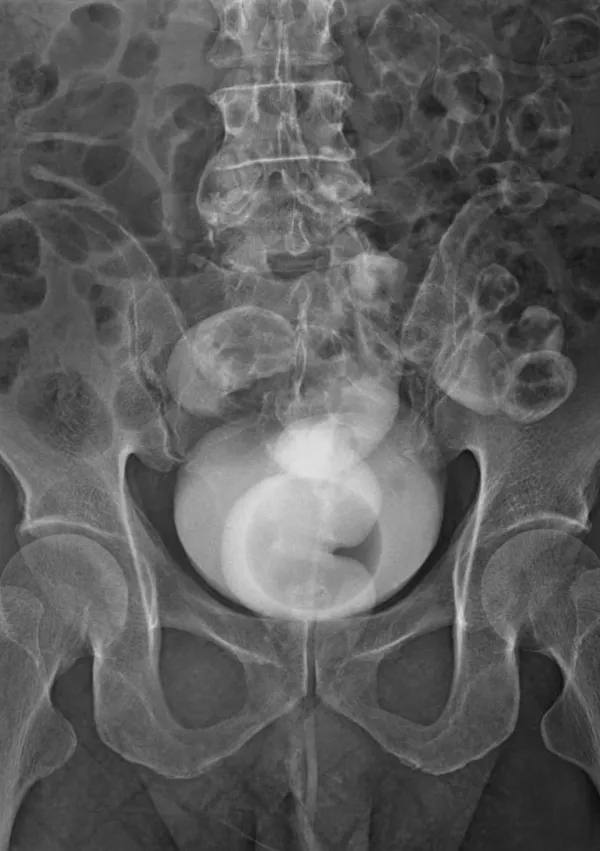

Diagnoza je bila neizprosna: descensus oziroma zdrs medeničnih organov. Njen mehur, maternica in danka so izgubili oporo in se povesili v vaginalni kanal. Spoznanje je bilo šokantno, toda za statistiko presenetljivo običajno.

To namreč ni osamljen primer. Ocenjujejo, da se bo kar 40 odstotkov žensk v svojem življenju srečalo z neko obliko zdrsa medeničnih organov. Gre za stanje, pri katerem podporna tkiva medeničnega dna – mišice in vezi, ki delujejo kot viseča mreža za organe – popustijo. Posledica je zdrs enega ali več organov (mehurja, maternice ali črevesja) navzdol proti vaginalni odprtini.

Rentgenska (simbolična) slika / Foto: Istock

Rentgenska slika / Foto: Istock